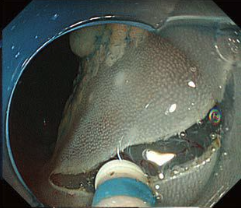

操作性と安全性の両立を目指した

2段階調整ナイフ切開ナイフ長は、KD-655Lは2mm、KD-655Qは1.5mm。

ナイフ格納時に0.1mmになる突出部が、マーキングや止血等をより安全にサポートし、1本でマーキングから切開・剥離までをサポートします。

上部消化管用と下部消化管用のナイフを

ラインアップ上部・下部消化管用スコープそれぞれに組み合わせてお使いいただけるよう、切開ナイフ長とシースの有効長が異なる2種類のナイフをラインアップしました。